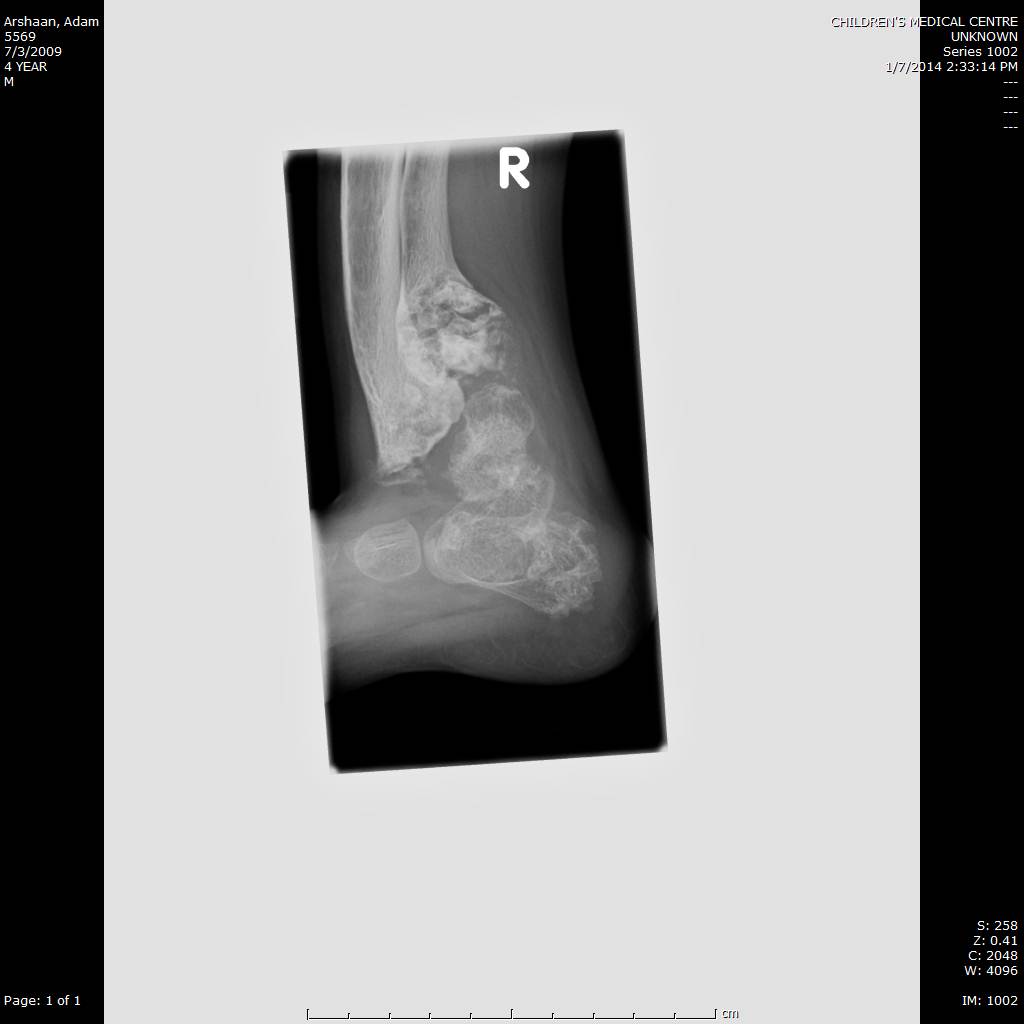

Here we share radiographic images to help with diagnosis of Jansen's disease:

Jansen's patients show extreme disorganization of the metaphyses of the long bones and of the metacarpal and metatarsal bones in sharp contrast to the almost normal appearance of the epiphyseal centers, which on x-ray appear widely separated from the long bones. The chin is receding. The fingers, especially the distal phalanges, are very short. The spine, pelvis, and lower legs are distorted.